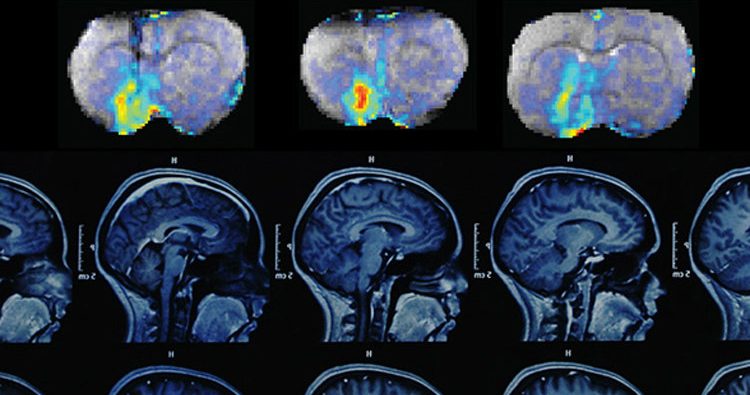

10. The brain is so plastic that it can rewire itself to let you have a normal life even after half of your brain is removed.

Hemispherectomy

Image Source: amegroups

Neuroplasticity is commonly observed in children who undergo hemispherectomy for epilepsy, a surgery that requires disabling half the brain or disconnecting the two cerebral hemispheres, and also in individuals who undergo surgery for brain trauma, stroke, epilepsy, or other such problems..(source)